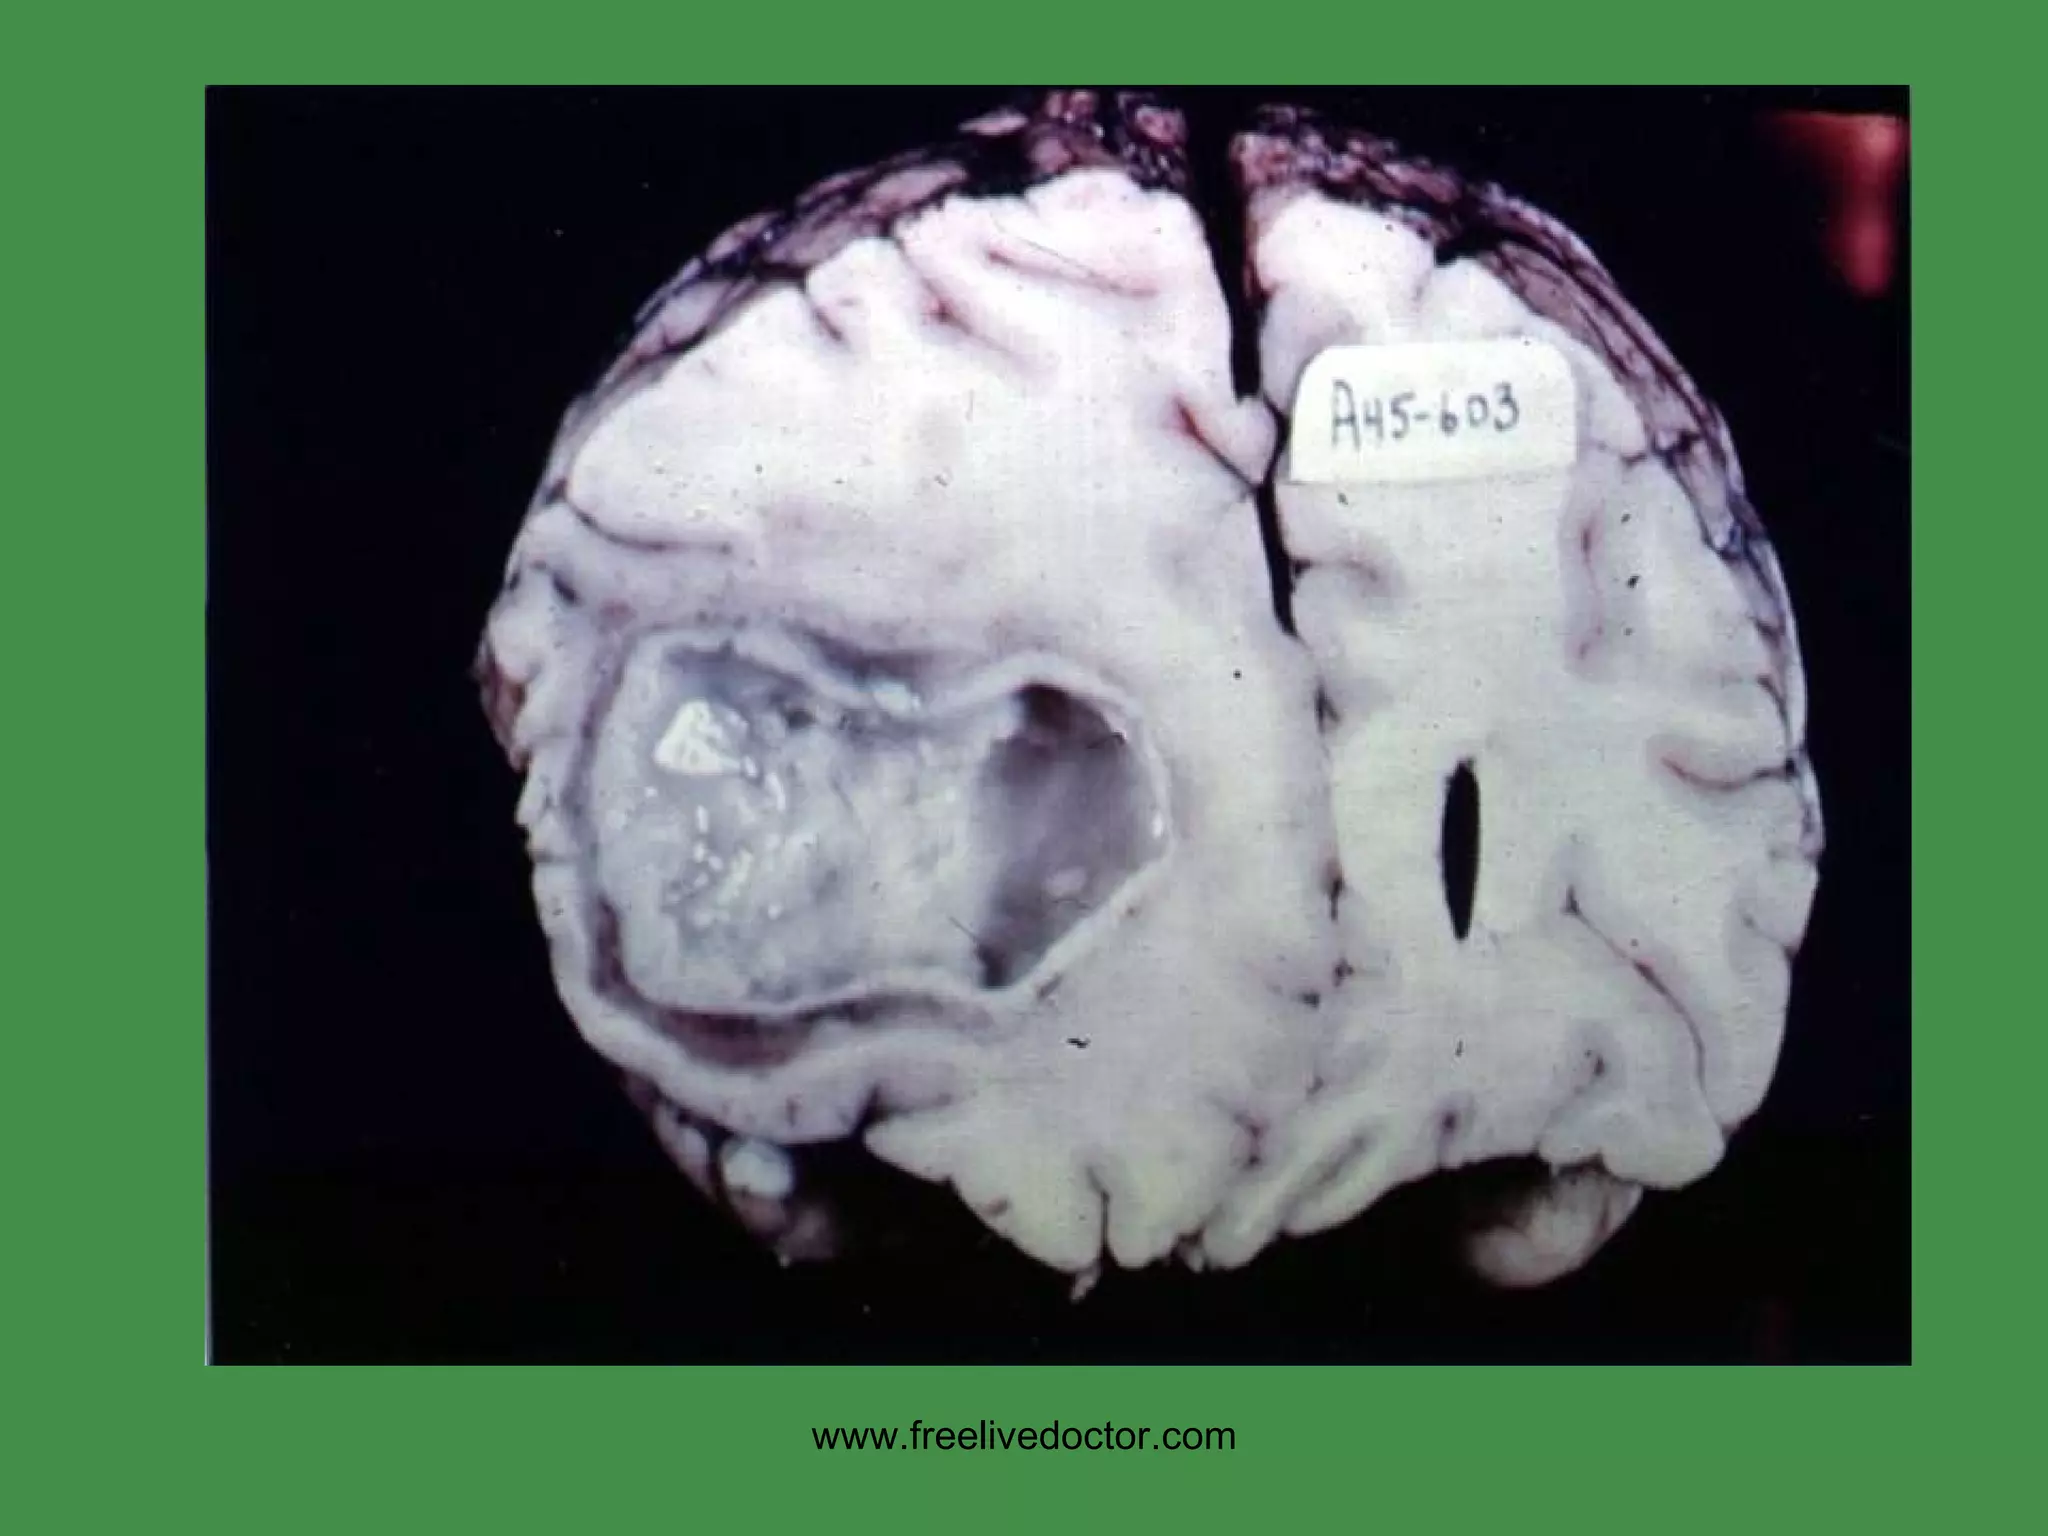

HYPERTENSIVE CVA Intracerebral Basal Ganglia Region (lenticulostriate arteries of internal capsule,  putamen) www.freelivedoctor.com

www.freelivedoctor.com

HYPERTENSIVE CVA www.freelivedoctor.com